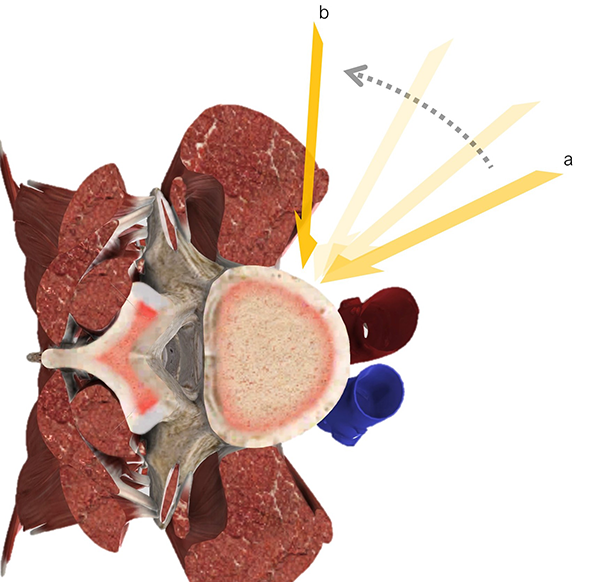

El disco es disecado con hisopos y maniobras romas. Esto permite evitar la lesión del plexo simpático que suele estar localizado en el fondo del corredor quirúrgico en relación a la cara anterior y lateral de la columna.11 La discectomía es realizada en forma estándar, comenzando con anulotomía con bisturí, pinza de disco y curetas. Es importante ampliar la anulotomía homolateral hacia posterior para poder utilizar de manera satisfactoria el instrumental de trabajo, los probadores y el implante definitivo. La denominada maniobra ortogonal se refiere al cambio que se realiza sobre la dirección del instrumental durante la preparación del espacio discal y la colocación del instrumental (Figura 6 y 7).

Figura 6: Esquema que representa la maniobra ortogonal. Obsérvese el cambio en el instrumental desde la dirección oblicua (a) a la ortogonal (b)

Esta se produce de manera tal que luego de haber iniciado la discectomía en la cara anterolateral del disco (posición oblicua), se profundiza la discectomía y se cambia la dirección del instrumental hasta colocarlo en la dirección habitual del acceso lateral directo, es decir en una posición perpendicular al eje sagital (posición ortogonal).

Si ello no ocurre, existe el riesgo de invadir el foramen contralateral o acceder en forma inadvertida al conducto raquídeo, ya sea con el instrumental, el implante o por protrusión del anulus junto con material discal. El trabajo del espacio discal realizarse de manera convencional. Bajo control radioscópico anteroposterior, se debe realizar la anulotomía contralateral.